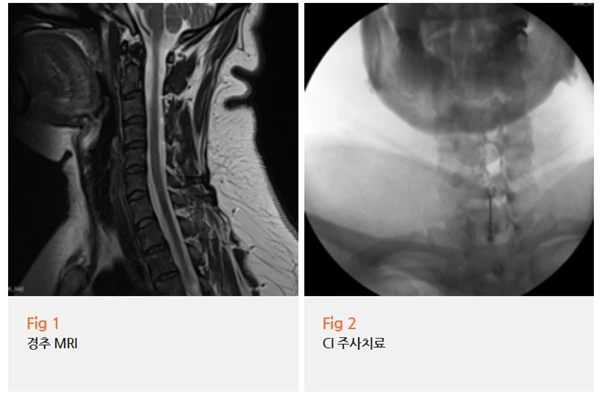

환자분께 당일 MRI 검사를 권해드렸어요.

결과는, 네.

목디스크가 맞았습니다.

환자분께 차근차근 설명드렸어요.

"여기 보시면 경추, 그러니까 목뼈 사이의 디스크에 경미한 변성이 보이시죠?

이 부분이 신경을 살짝 건드리고 있어요.

그래서 겨드랑이 쪽으로 통증이 뻗어나가는 거예요."

신경이 눌리거나 자극받으면 그 신경이 담당하는 부위에

'방사통'이라는 게 생기는데요.

이게 마치 전기가 흐르는 것처럼 느껴지는 경우가 많습니다.